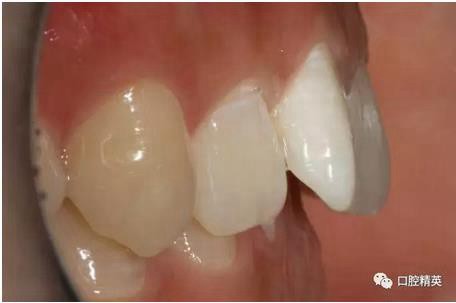

口內(nèi)正側(cè)位及切端特寫

從側(cè)位照可看出遠(yuǎn)中切角略有回收